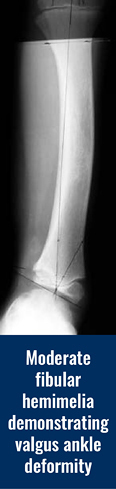

The fibula (small bone in the lower leg) can be partially or totally absent. When the fibula is totally absent on the X-rays, there is always a fibrous remnant connected to the calcaneus (heel bone) that is very tight and contracted. This fibrous fibula remnant is called the fibular anlage. This tight band of tissue causes the foot and ankle to rotate outwards and the lower leg to grow in a valgus (knocked knee) direction. The foot’s toe down position (equinus contracture) is caused by the malalignment (misdirection) of the ankle joint and the tight heel cord/calf muscle. The ankle joint not only points down, but it also points in an outward direction. This is termed ankle valgus. When severe ankle valgus is present, this gives the appearance that the patient is walking on the inner side of the ankle. The ankle position is a combination of the above stated factors that are all related to fibular hemimelia.

The ball-in-socket configuration allows for all of the normal ankle motion of toe up (dorsiflexion) and toe down (plantar flexion) along with the side-to-side rocking motion (eversion and inversion) to come from one joint instead of two joints in a normal ankle. The benefit of this ball-in-socket adaptation is to allow all “normal” motion that a normal ankle would possess. The disadvantage of this ball-in-socket ankle joint is the potential for the foot and ankle to angle outward giving a “squashed” foot/ankle appearance that is termed dynamic ankle valgus. Dynamic means that the deformity appears when the joint is stressed by weight bearing. Ankle valgus means a “knocked knee” appearance of the ankle.